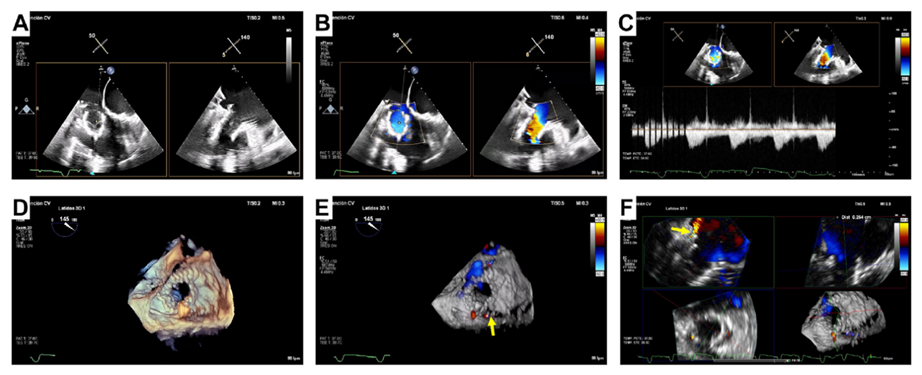

基線經(jīng)胸和經(jīng)食道超聲

術后經(jīng)食道超聲,僅微量瓣周漏

起搏器/ICD導線引起的TR是三尖瓣反流的主要機制,這也是三尖瓣介入治療面臨的極大挑戰(zhàn)。既往臨床實踐已證實LuX-Valve系列產(chǎn)品在高危三尖瓣反流患者中的安全性和有效性,并且術后并發(fā)癥發(fā)生率低。LuX-Valve系列產(chǎn)品瓣膜應用室間隔“錨定區(qū)域”作為特殊的錨定機制,保證了瓣膜的穩(wěn)定性。同時,多種尺寸的、較大的自適應防漏環(huán)可有效避免瓣周漏的發(fā)生,所以對于術前有起搏器/ICD植入史的患者,LuX-Valve系列產(chǎn)品可以最大程度減少由導線引起的三尖瓣殘余反流。本文報道的病例有兩根導線,其中一根材質(zhì)較厚,位置在瓣膜的中心,手術的結(jié)果依然很完美。尤其是,LuX-Valve系列產(chǎn)品經(jīng)導管三尖瓣置換系統(tǒng)的調(diào)整和釋放是在緩慢而完全受控的情況下進行的,術者可精確定位和控制導線的位置。隨訪期間,LuX-Valve Plus瓣膜沒有出現(xiàn)衰敗或血栓的現(xiàn)象,患者生活質(zhì)量也大為改善。